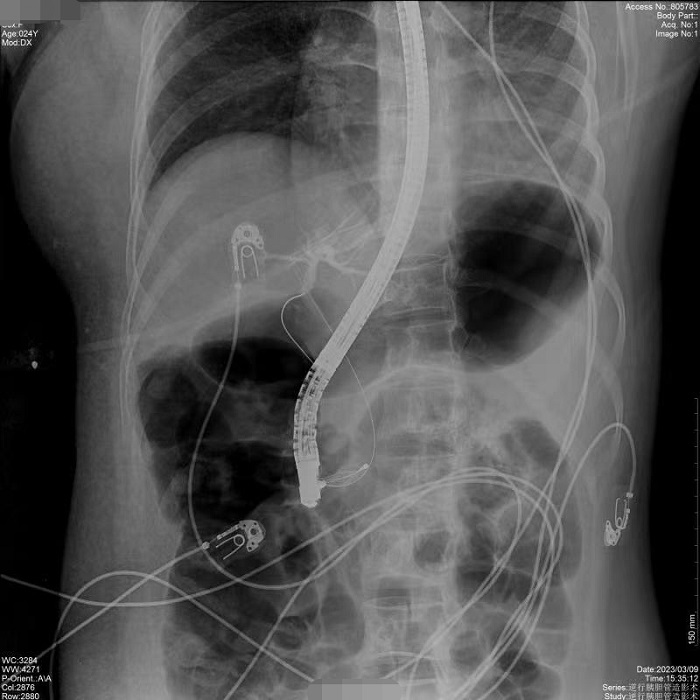

病例1:患者間斷上腹部脹痛4月,經(jīng)磁共振膽道水成像(MRCP)明確為膽總管結(jié)石、膽囊結(jié)石。常規(guī)手術(shù)需要膽總管切開取石,考慮其自身的訴求,醫(yī)生決定嘗試為患者做內(nèi)鏡逆行膽管造影術(shù),幫助實(shí)現(xiàn)最小創(chuàng)傷及快速康復(fù)。術(shù)中,通過十二指腸鏡,將導(dǎo)絲通過十二指腸乳頭(即膽總管的下端開口處)置入膽管內(nèi),在X線透視下注射造影劑造影,完成對(duì)膽總管內(nèi)情況診斷,并在診斷基礎(chǔ)之上完成取石治療。